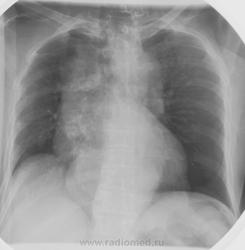

Пацинтка 60 лет. Остро возникшая нижняя параплегия. (3 дня). Рентгенограммы выполнены в положении лежа.

Первый вопрос который возникает- где раположена тень в лёгком или в средостении? Скорее всего в средостении ( но, может оказатьс и в лёгком...). Тогда чем обусловлен субстрат тени?

"Зло", наиболее вероятно из средостения.

Средостение расширено, больше справа, расширено равномерно. Создается впечатление наличия и гиперплазированных лимфатических узлов, и не только лимфоузлов (внутригрудных) общепринятых групп, но и пониже.

Плохо вижу задние фрагменты ребер справа медиально, по всей видимости, задействовано заднее средостение. Конечно, если бы не возраст, можно было предположить герминогенную группу, но возраст не дает об этом подумать.

больших остаточных туберкулезных изменений в правом гемитораксе в виде множественных петрификатов в лимфатических узлах и крупного очага Гона  не позволяет, так просто, исключить   специфическую природу видимых поражений и нижнию параплегию.

yes. Частично внутригрудной желудок

Несомненно сочетание патологии.

К позвонкам стоит присмотреться

Литический метастаз Th11.

Рак щитовидной железы. Диагноз верифицирован гистологически. Ответ биопсии получен вчера и из железы и из позвонка